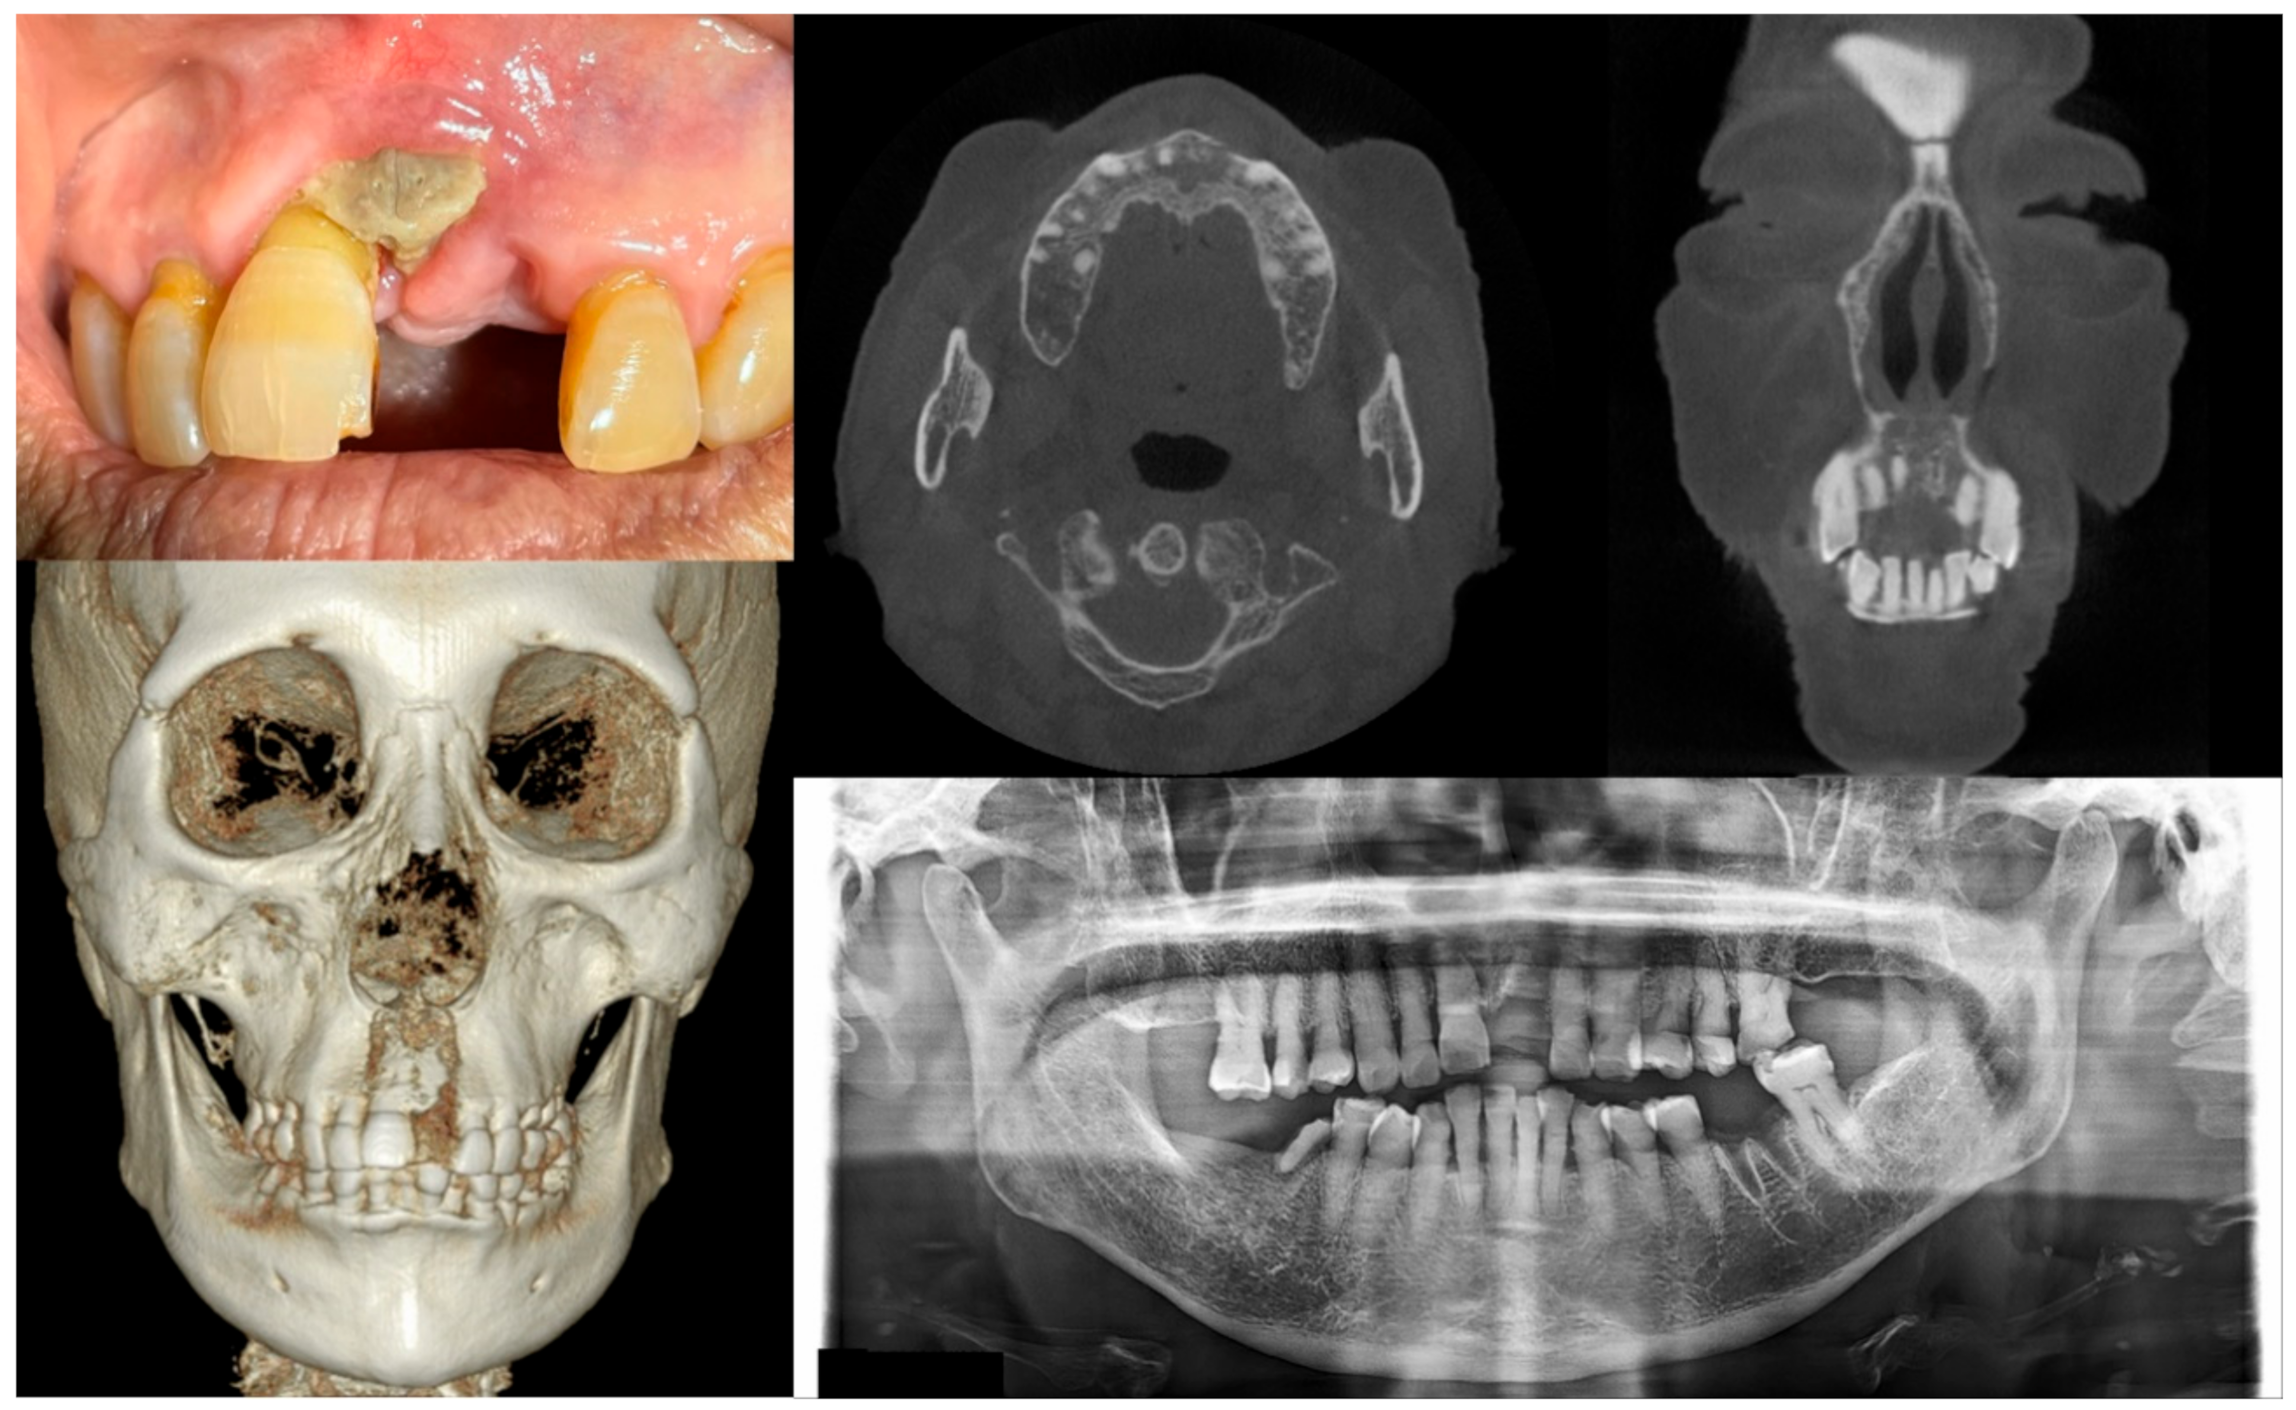

2.1. Staging of MRONJ and Treatment Strategies

| Stage | Clinical Manifestation | Strategies for Management |

|---|---|---|

| At risk | No apparent necrotic bone | Patient education, no treatment required |

| 0 | No clinically necrotic or exposed bone with nonspecific clinical and radiographic findings | Systemic medication, including antibiotics and pain-killers when indicated |

| 1 | Exposed necrotic bone or intraoral fistula with no symptoms and no infection | Patient education, oral antibacterial rinse, close clinical follow-up |

| 2 | Exposed necrotic bone or intraoral fistula showing symptoms and signs associated with infection | Antibacterial oral rinse, systemic medication with antibiotics and pain-killers, debridement reducing the volume of necrotic bone for infection control |

| 3 | Exposed necrotic bone or intraoral fistula showing symptoms and signs associated with infection + exposed necrotic bone invading the inferior border of the mandible or the sinus floor of the maxilla and/or extraoral fistula and/or oroantral fistula | Antibacterial oral rinse, medication with antibiotics and pain-killers, surgical treatment including open debridement/resection for long-term control of symptoms and infection |